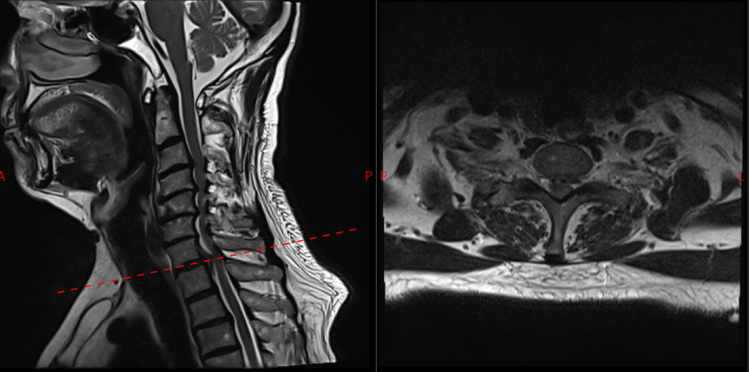

面对这一特殊情况,吴静晔主任没有急于下结论,而是为患者进行了细致全面的检查,最终精准诊断为脊髓型颈椎病。而进一步检查显示,患者存在C3-T1多节段狭窄,病情复杂且手术节段较多,这无疑给治疗带来了巨大挑战。

常规的治疗方案是颈后路C3-T1开门手术。虽能实现彻底减压,但手术损伤较大,对于78岁高龄的患者来说,是极大的考验。

为最大程度降低手术损伤,保障手术安全,吴静晔主任、王肖虎主任带领团队反复研讨,最终制定了更贴合患者情况的手术方案——C7-T2节段全椎板切除减压、髓核摘除、椎弓根螺钉内固定术。